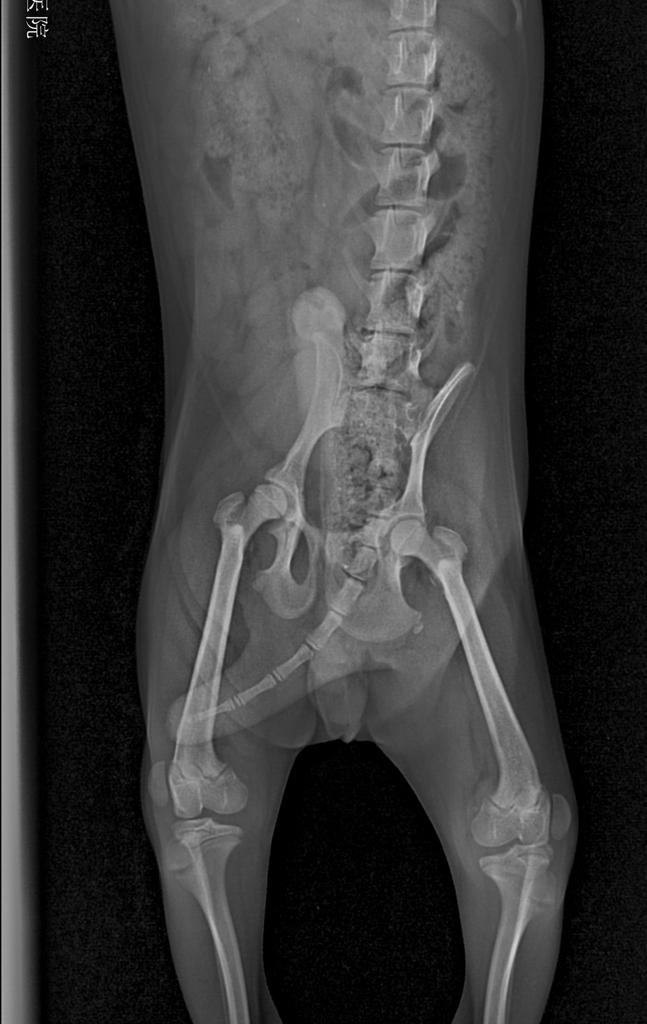

根据主人的症状描述,没有任何外伤和刺激狗狗突然后腿不敢着地,然后跑起来会自行恢复,配合宠物医生的髌骨部位触诊,以及照射x光后,即可确诊。

髌骨脱位按症状和髌骨脱出的程度划分为四级

★第一级,狗狗基本没有症状,可能只是在体检的时候发现,在日常睡觉后偶尔出现后肢抬起不敢着地,但是很快就恢复。(宠物医生检查时,可以把髌骨推出滑车沟,但是髌骨可以自行恢复)

★第二级,这也是宠物主人最常见的一级表现,狗狗经常出现三条腿站立,跛行,跑动的时候可以自行恢复,但是还不定时的经常出现这个症状(宠物医生可以轻松推出髌骨,但是狗狗在伸展腿部的时候可以自行复位。)

★第三级 狗狗的三条腿症状和跛行长期保持,即使跑动的时候也不会改变(髌骨不用宠物医生推就长时间在外边,需要宠物医生辅助可以归位,但是一松手就又脱出)

★第四级 也是最厉害的了,狗狗已经出现严重症状,即使靠人工也无法恢复髌骨到滑车沟里面,这个时期的狗狗基本都出现了严重的肢体变形,比如内八字变形。